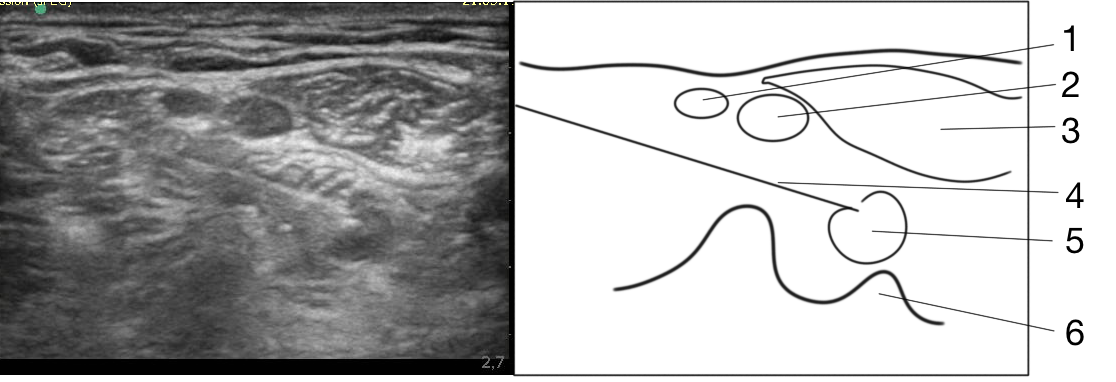

In Group 3, IBPB was performed under US navigation (Sonosite M-Turbo: 12 MHz linear sensor, transverse scanning at the level of the С6–С7 vertebrae with lateral access and long-axis imaging of the needle) and neurostimulation (Stimuplex HNS12, 0.5 mA, 1 Hz, 0.1 ms) with a selective block of the brachial plexus trunks. This was achieved by repeatedly repositioning the needle and introducing individual boluses of local anesthetic, not exceeding 0.5–1 mL, from each position. The solution was distributed around each trunk of the brachial plexus, which determined the necessary volume of local anesthetic. In total, 7–10 mL of 0.5% ropivacaine for block of the brachial plexus (Fig. 1) and 5–7 mL of 0.2% ropivacaine for the block of the superficial branches of the cervical plexus were used [15].

Fig. 1. Block of the upper, middle (a), and lower (b) trunks of the brachial plexus with lateral access: 1, the upper trunk of the brachial plexus; 2, the middle trunk of the brachial plexus; 3, the anterior scalene muscle; 4, needle; 5, the lower trunk of the brachial plexus; 6, the C7 vertebra